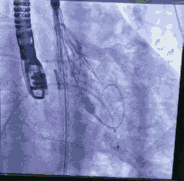

采用右股动脉为主入路,左股动脉为冠脉保护预留。先尝试干预PL慢性闭塞病变,XT-R导丝通过闭塞病变,在球囊锚定下,1.25球囊通过病变扩张。复查造影显示闭塞远端血管细小,放弃进一步干预右冠。

顺利跨瓣,测得跨瓣压差62mmHg。送20mm球囊扩张主动脉瓣,经右桡动脉猪尾导管造影,冠脉切线位未见右冠脉显影。为策安全,决定对RCA行冠脉保护,送JR4导管及guidzila和3.5球囊行冠脉保护。置入24mm微创 vitaflow瓣膜标准位释放。复查造影显示少量主动脉瓣返流,左右冠显示良好,撤除右冠保护。术后测压差为10mmHg。缝合双侧股动脉。术后恢复良好,次日转回普通病房,顺利出院。